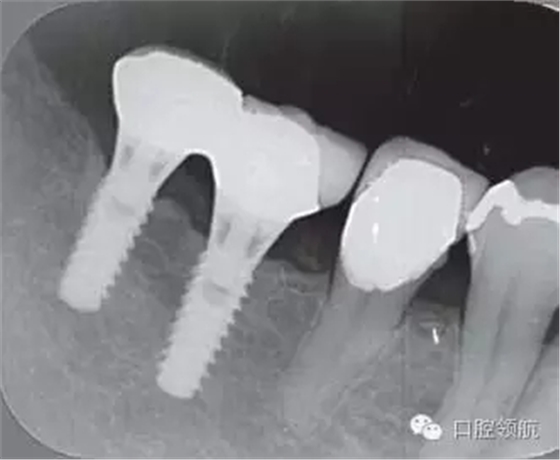

2005年4月時,可見(左下第6顆牙) 部的種植體達到第4螺紋,(左下第7顆牙)的種植體周圍觀察到位于第3螺紋的頸部進行性骨吸收(圖4)。到2009年9月時,骨吸收像的周圍有了明顯的骨密度增加影像(圖5)。

圖4 (左下第6顆牙)的種植體達到第4螺紋, 7 的種植體達到第3螺紋的頸部進行性骨吸收現(xiàn)象(2005年4月)。

圖5 骨吸收像的周圍有了明顯的骨密度增高影像(2009年9月)